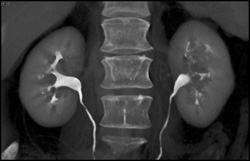

Bilateral Renal Artery Stenosis